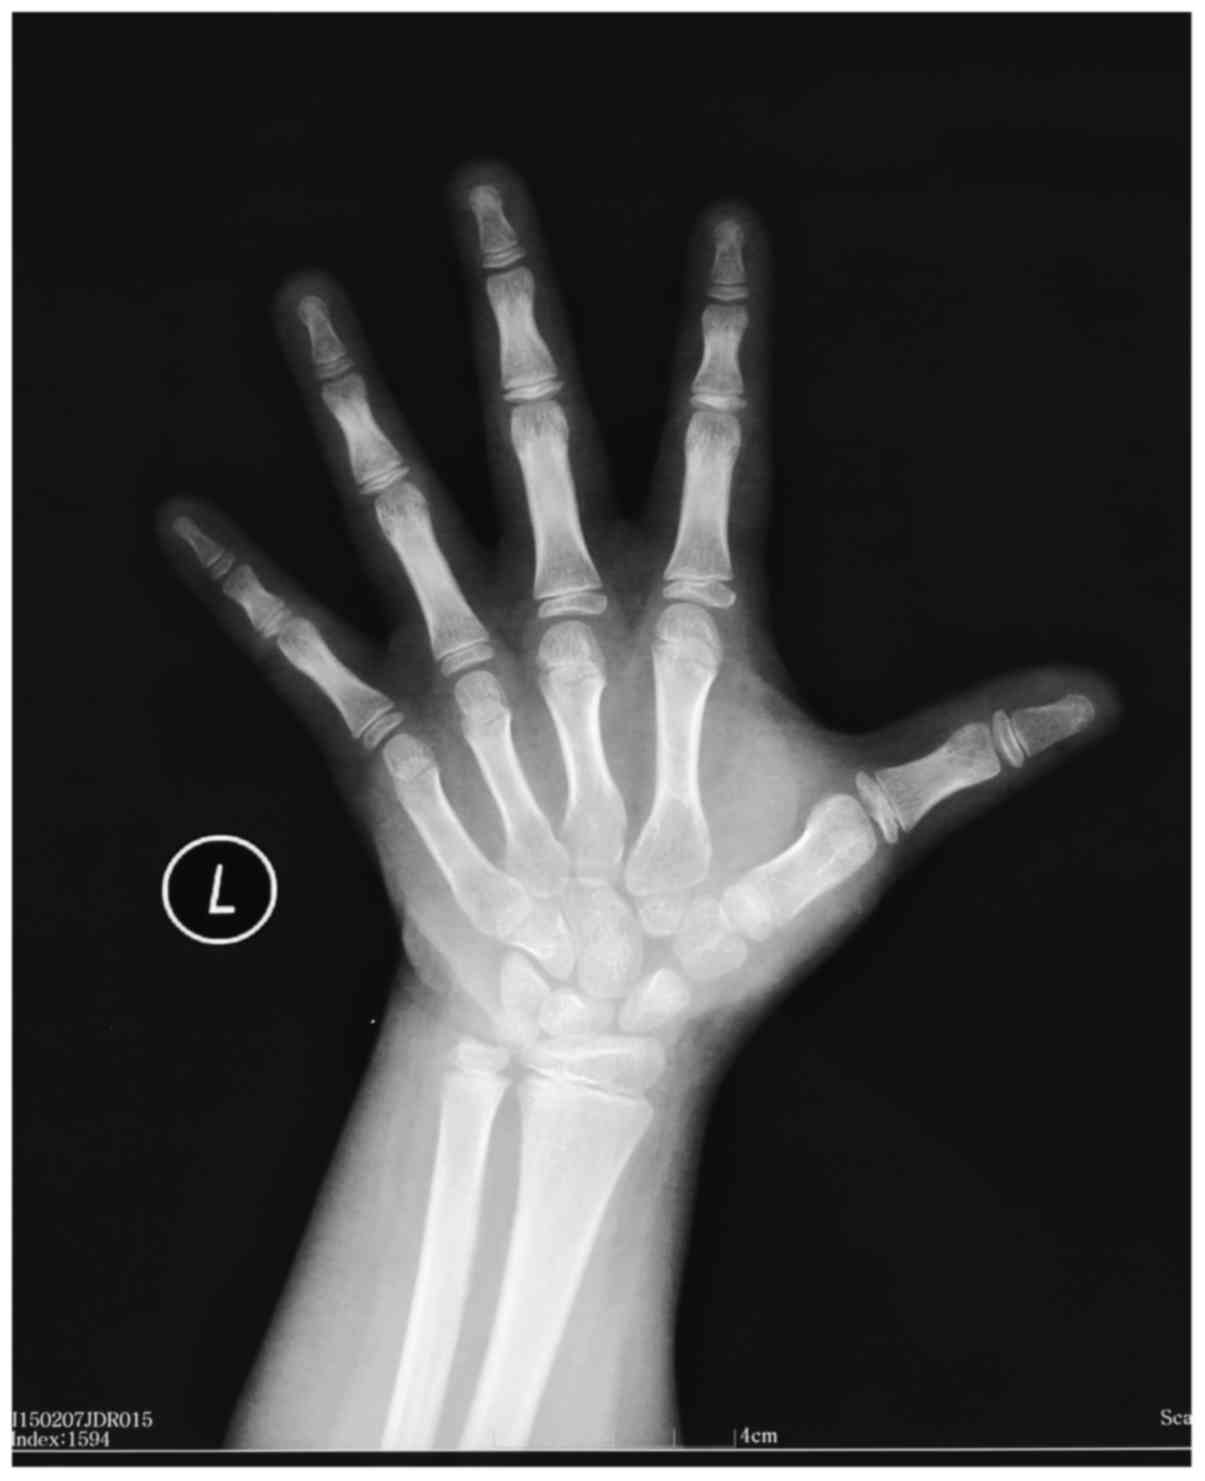

A 14-year-old male patient of non-consanguineous parents was referred to the Department of Pediatrics of the General Hospital of Tianjin Medical University (Tianjin, China) due to obesity, short stature and muscle weakness in February, 2014. He had shown progressive weight gain, delay in growth, constipation, muscle weakness and poor academic scores over the past 3–4 years. Physical examination results were as follows: Body temperature, 36.5°C; heart rate, 60 beats per min; respiratory rate, 20/min; blood pressure, 100/70 mmHg; body weight, 59 kg (>97th percentile); height, 139 cm (<3rd percentile); and body mass index, 30.5 (>97th percentile). The thyroid gland was enlarged. Abdominal examination indicated hepatomegaly and cardiac examination indicated a slightly distant heart sound without murmurs. The bilateral testicular volume was 25 ml as measured by a Prader orchidometer (Creative Health Products, Ann Arbor, MI, USA) and stretched penile length was 5 cm. No pubic or axillary hair was observed. Laboratory results are summarized in Table I. Laboratory parameters associated with renal function were normal. Thyromegaly accompanied with low-intensity echoes were identified by thyroid ultrasound. Abdominal ultrasound revealed hepatomegaly. Delayed bone age was confirmed according to X-ray imaging of the left wrist and hand (Fig. 1) with an estimated bone age of 10 years. Cranial magnetic resonance imaging (MRI) indicated enlargement of the pituitary gland (Fig. 2), and pituitary hyperplasia was suspected. Based on these results, the patient was finally diagnosed as VWGS. As a treatment, replacement therapy was given using levothyroxine with an initial dose of 25 µg/m2/day, which was gradually increased to 100 µg/m2/day. The patient was followed up for 6 months and the levels of free triiodothyronine (T3), T4 and TSH were 4.35 pmol/l, 18.65 pmol/l and 3.31 µIU/ml, respectively. The body height showed an increase of 5 cm after the treatment.

Figure 1.

X-ray indicated delayed bone age in left wrist compared with the actual age (10 vs. 14 years).